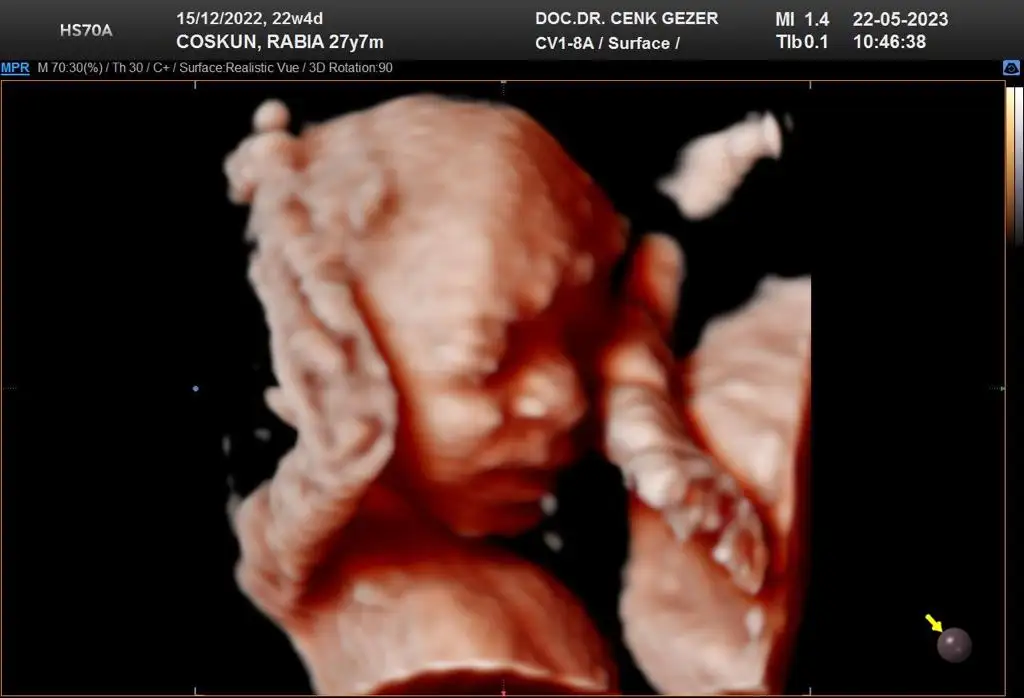

Ooy maaşallahKızlar Aybars'ım ancak bu kadar gösterdi suratınıçevremdeki herkes yanaklarının tombişliği ve burnunu aynı bana benzetti ama daha erken mi bunun için bilemiyorum ama nasıl mutlu oldum anlatamam